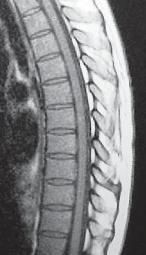

МРТ № 51

На МРТ № 51 наблюдается грудной отдел позвоночника с нормально выраженным физиологическим кифозом, межпозвонковыми дисками и спинным мозгом.

Рассмотрим вариант нормы и патологии грудного отдела позвоночника (МРТ № 51, МРТ № 52). Конечно, заболеваний, которые могут проявиться вследствие развития остеохондроза грудного отдела позвоночника, достаточно. В каждом отдельном случае необходимо установить точный диагноз, осуществить грамотный подход в выборе методов лечения. Нельзя недооценивать возможные вариации развития заболевания. Вот, например, из-за таких деформаций позвоночника, которые можно наблюдать на МРТ № 52, порой возникают парезы или параличи, зачастую вследствие развивающегося ишемического «миелита», точнее спондилогенной миелопатии — перерождение вещества спинного мозга из-за недостаточного кровоснабжения. Причём то же клиническое течение спондилогенной миелопатии может протекать двояко. Чаще заболевание развивается исподволь, постепенно в течение довольно длительного времени. Порой останавливается, так и не достигнув своего апогея. А бывает (хотя и намного реже) в течение относительно короткого отрезка времени, на фоне полноценной функции спинного мозга, возникают парезы и параличи. Что лежит в основе этого тяжелейшего осложнения — спондилогенной миелопатии? Как правило, расстройство кровоснабжения спинного мозга. Оно, в свою очередь, возникает вследствие нарушения проходимости питающих его артериальных кровеносных сосудов. Опасность здесь таится в том, что значительный по длине спинной мозг, занимающий почти всю протяжённость позвоночника, получает кровоснабжение всего из нескольких артерий. Если даже одна из таких питающих артерий вследствие перерастяжения или сдавления «закупоривается», то значительные территории спинного мозга лишаются кислорода, питательных и других веществ, что приносит с собой его тканям артериальная кровь. Нарушение проходимости питающих спинной мозг кровеносных сосудов возникает вследствие их перерастяжения вместе со спинным мозгом и его элементами, что или приводит к сужению просвета растянутого артериального ствола или к прямому сдавлению его деформированными костными структурами позвоночника. Нервная ткань спинного мозга очень чуткая к недостаточности кровоснабжения и быстро гибнет в условиях неполноценного притока артериальной крови. Это, в свою очередь, приводит к возникновению частичных и полных параличей тех органов, которые зависят от поражённых территорий спинного мозга. Вот такая выстраивается цепочка, где одно событие неумолимо порождает другое и приводит к определённым последствиям.